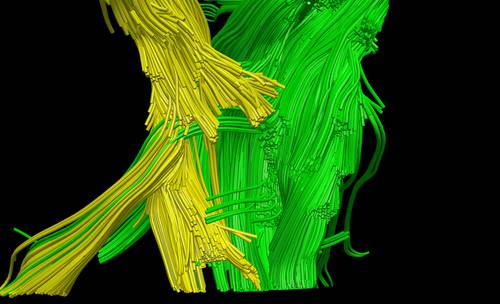

En esta concepción artística, proporcionada por el laboratorio Schneider de la Universidad de Pittsburg, se muestra lo que sería un escáner del daño a las fibras nerviosas del cerebro luego de un traumatismo

Permite disecarlo, conservarlo y entenderlo de forma tridimensional, explica José Figueroa Gutiérrez